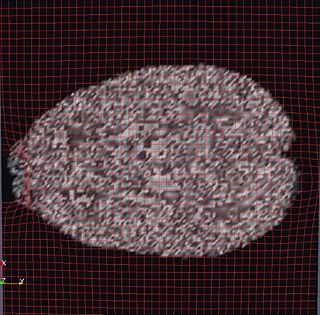

OMT Deformation Grid on MRI

OMT Deformation Grid on DWI